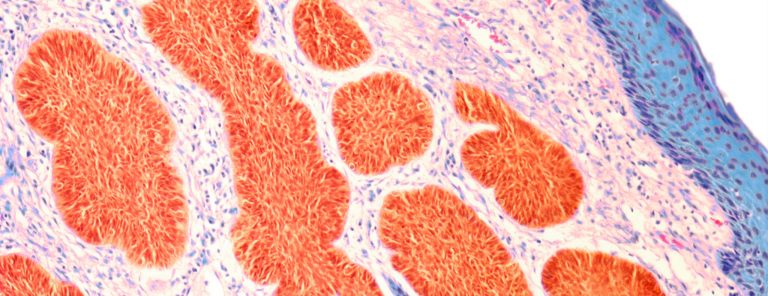

فالجنين في الشهر الأول، ما هو إلا نقاط متجمعة من الدماء، وإن قامت المرأة بشرب الكثير من السوائل الساخنة أو حتى الاستحمام بالماء الساخن فإنّ ذلك قد يعرضها لفقدان الجنين، لأنه في مرحلة صغيرةٍ جداً، ولا يمكن أن نحتسبه أنه إنسان، وعليه لا بدّ من التعامل مع هذه النقطة والتوقف عن الاستهتار.